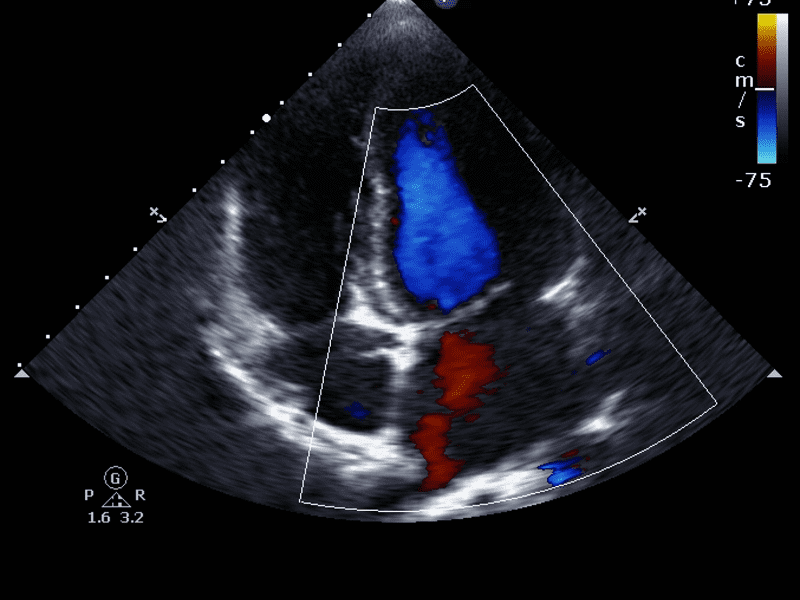

- Il colore viene utilizzato per rappresentare la direzione del flusso (rosso per il flusso verso la sonda, blu per il flusso lontano).